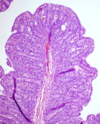

What lesion is shown here? (The slide is from an intestine)

atrophic enteritis

40

What lesion is shown here?